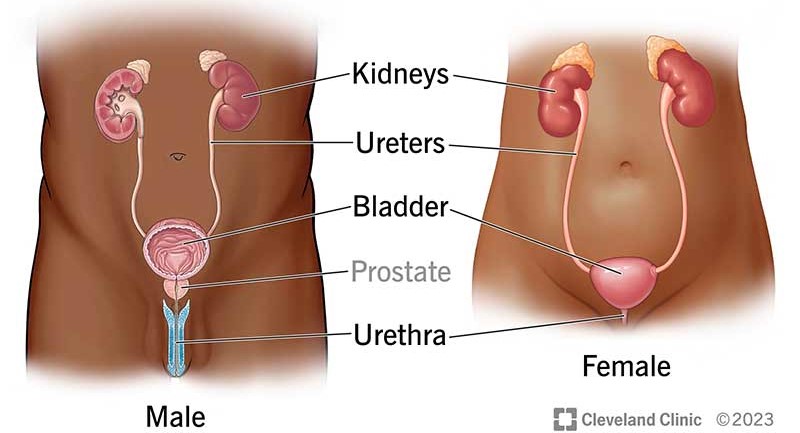

urinary tract